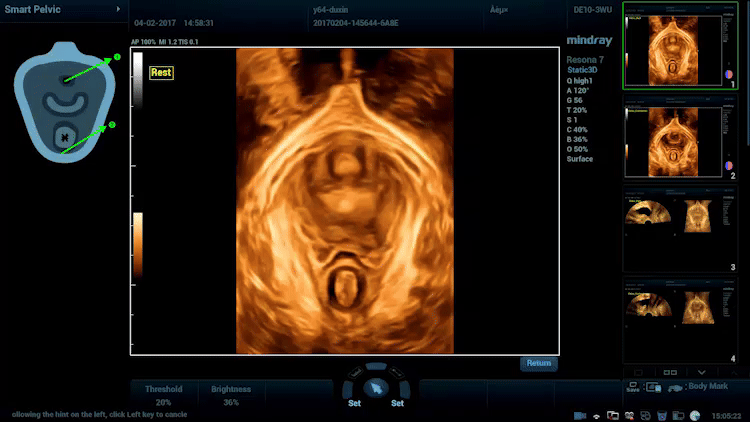

Smart Pelvic

Nhận thấy tầm quan trọng ngày càng tăng của siêu âm trong chẩn đoán các rối loạn sàn chậu, Smart Pelvic mang đến một giải pháp mới giúp đơn giản hóa đáng kể quy trình thao tác và rút ngắn thời gian thăm khám cho một đánh giá chuẩn hóa về sàn chậu. Với thao tác cực kỳ đơn giản cho người dùng, hệ thống sẽ tạo ra một hệ tọa độ chuẩn và tự động cung cấp tất cả các phép đo liên quan chỉ trong vài giây.